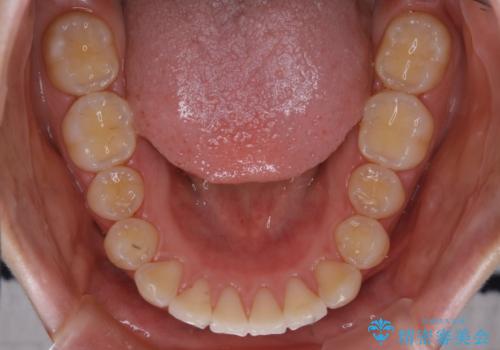

- 前歯の重なりが気になるとご相談にいらした方です。前歯のがたつきは奥歯の噛み合わせのズレが原因となっていたため、インビザラインFULLにて奥歯からしっかり治療していきました。

前歯のがたつきだけを治そうとした場合、噛み合わせは二の次なってしまう事が多く、せっかく綺麗になった歯並びも後戻りしやすくなります。

見た目だけでなく奥歯を移動させて噛み合わせの改善までが行えるのはインビザラインであるからこそです。奥歯の噛み合わせからしっかり機能させることで、長期間にわたって綺麗な歯並びを保ちやすくなります。